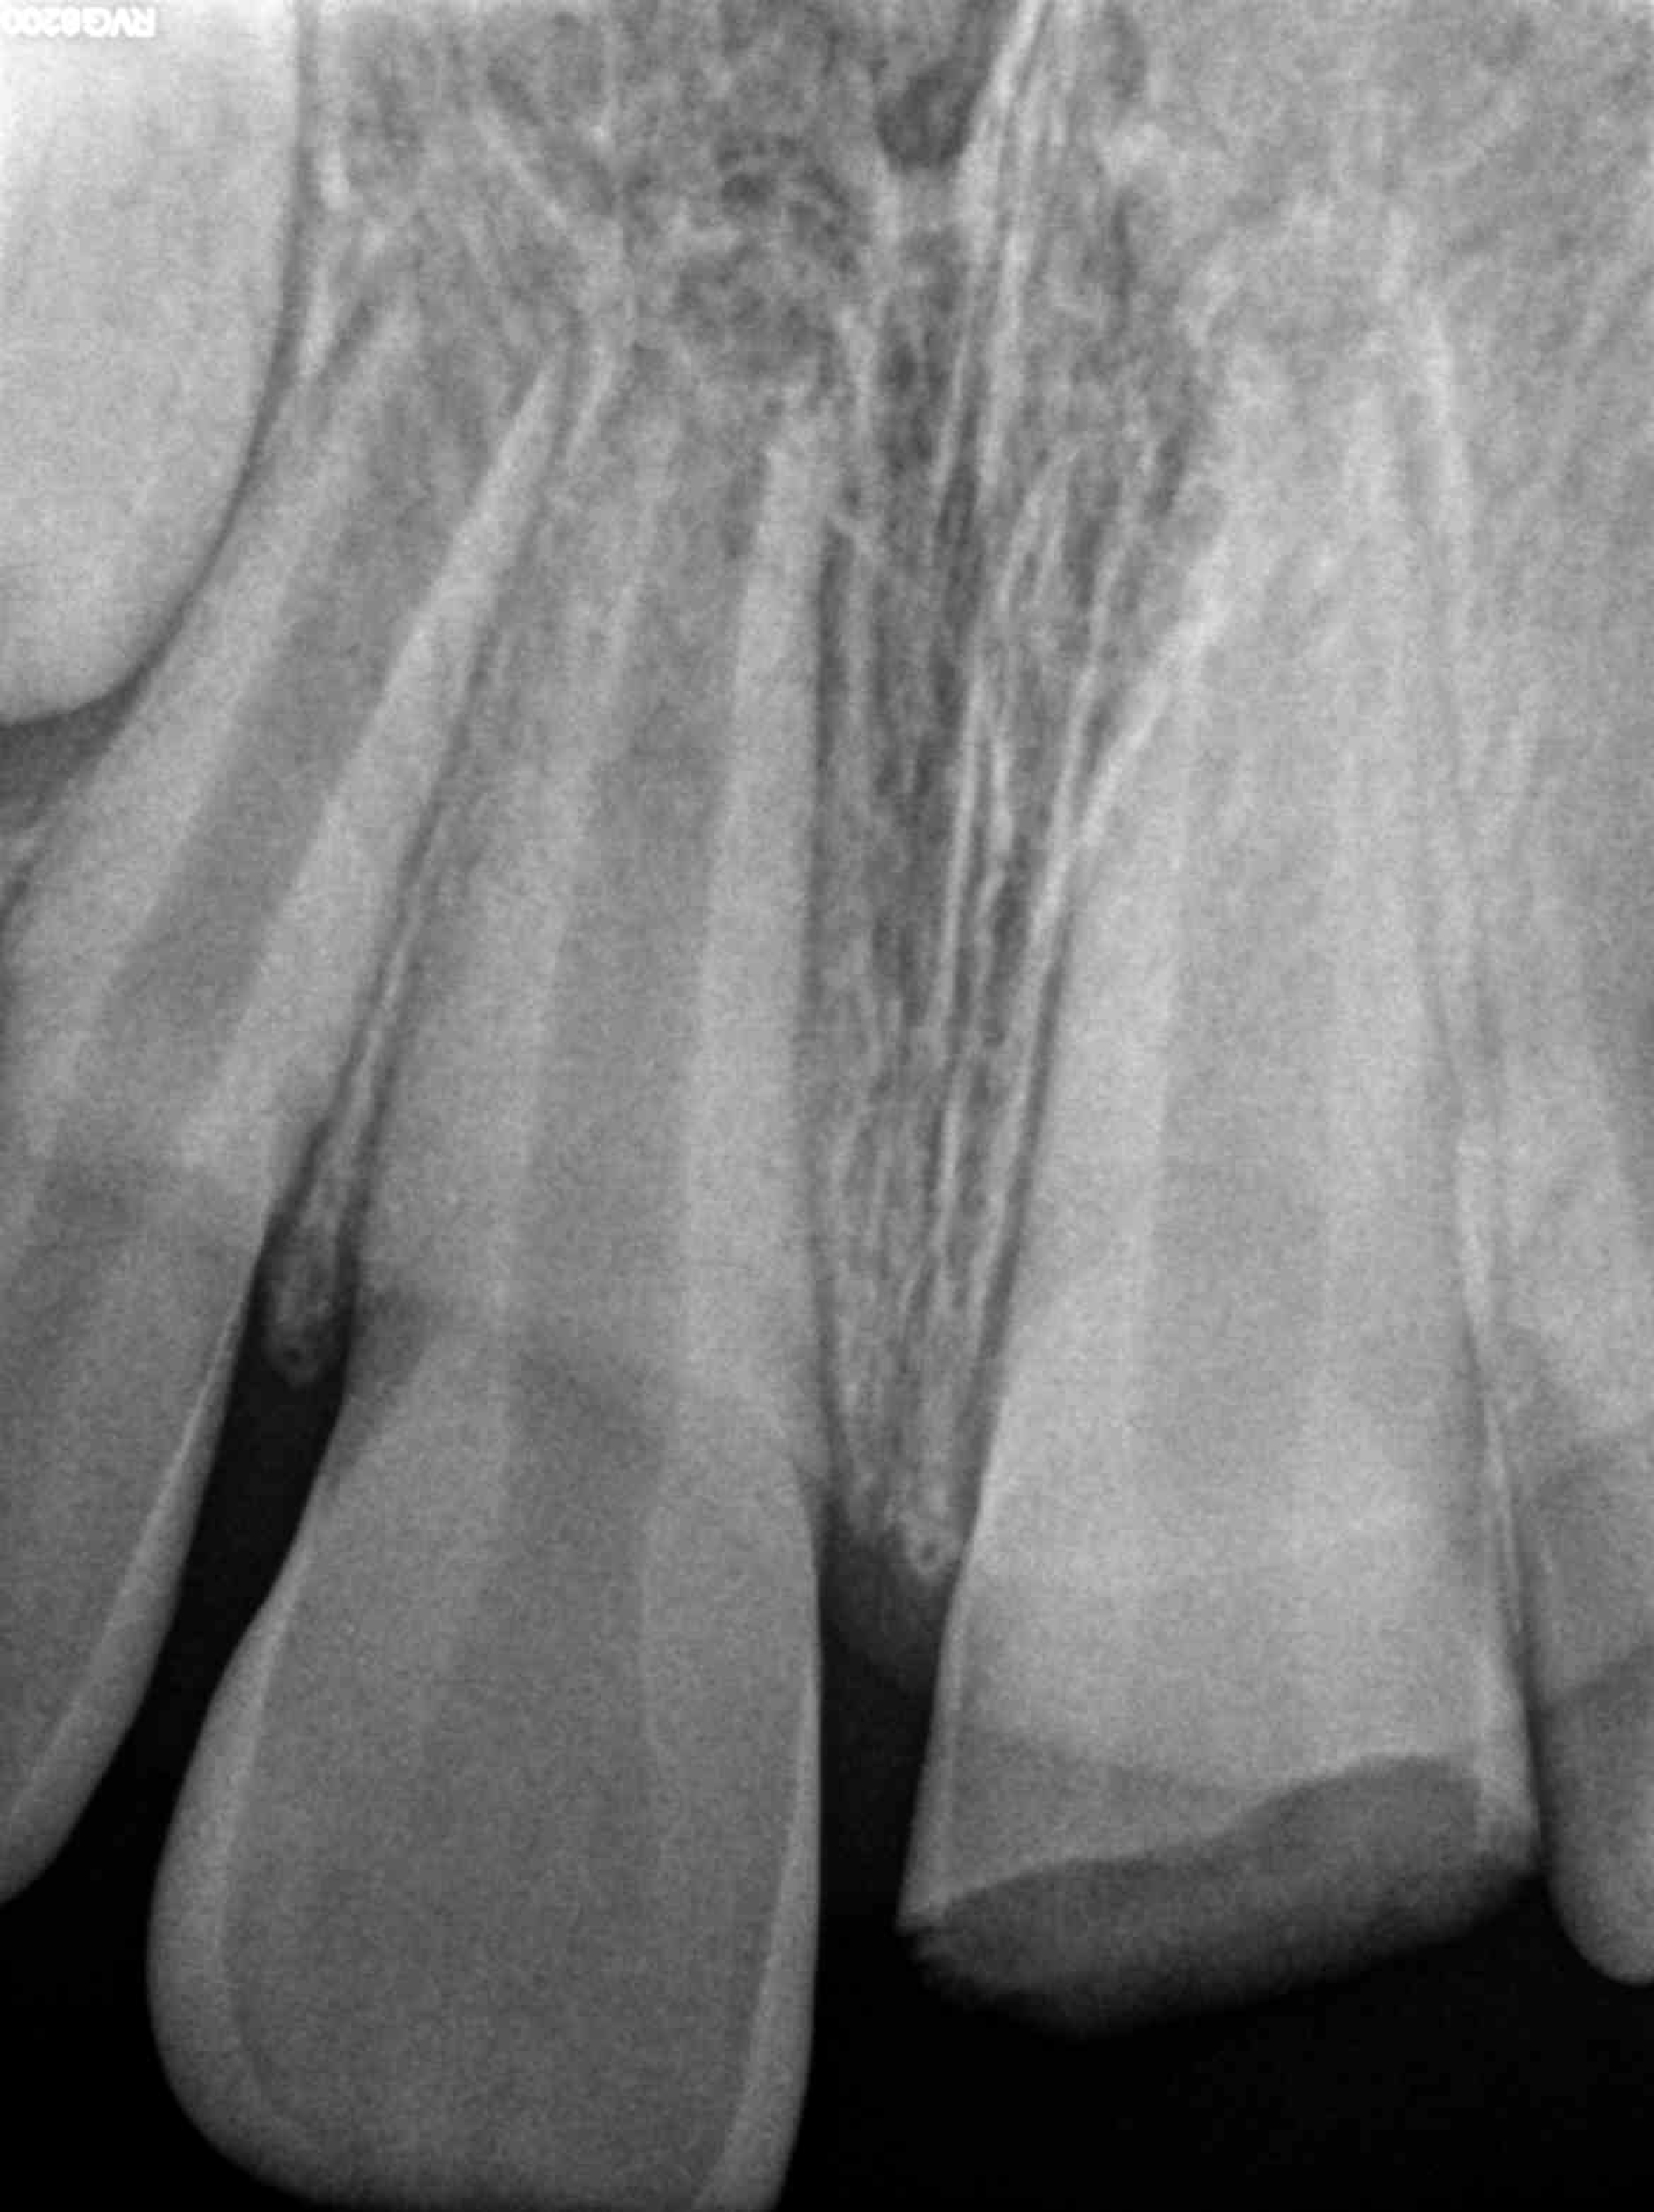

2.1 fractura coronal

Endodoncia y Traumatología Dental

Radiografías